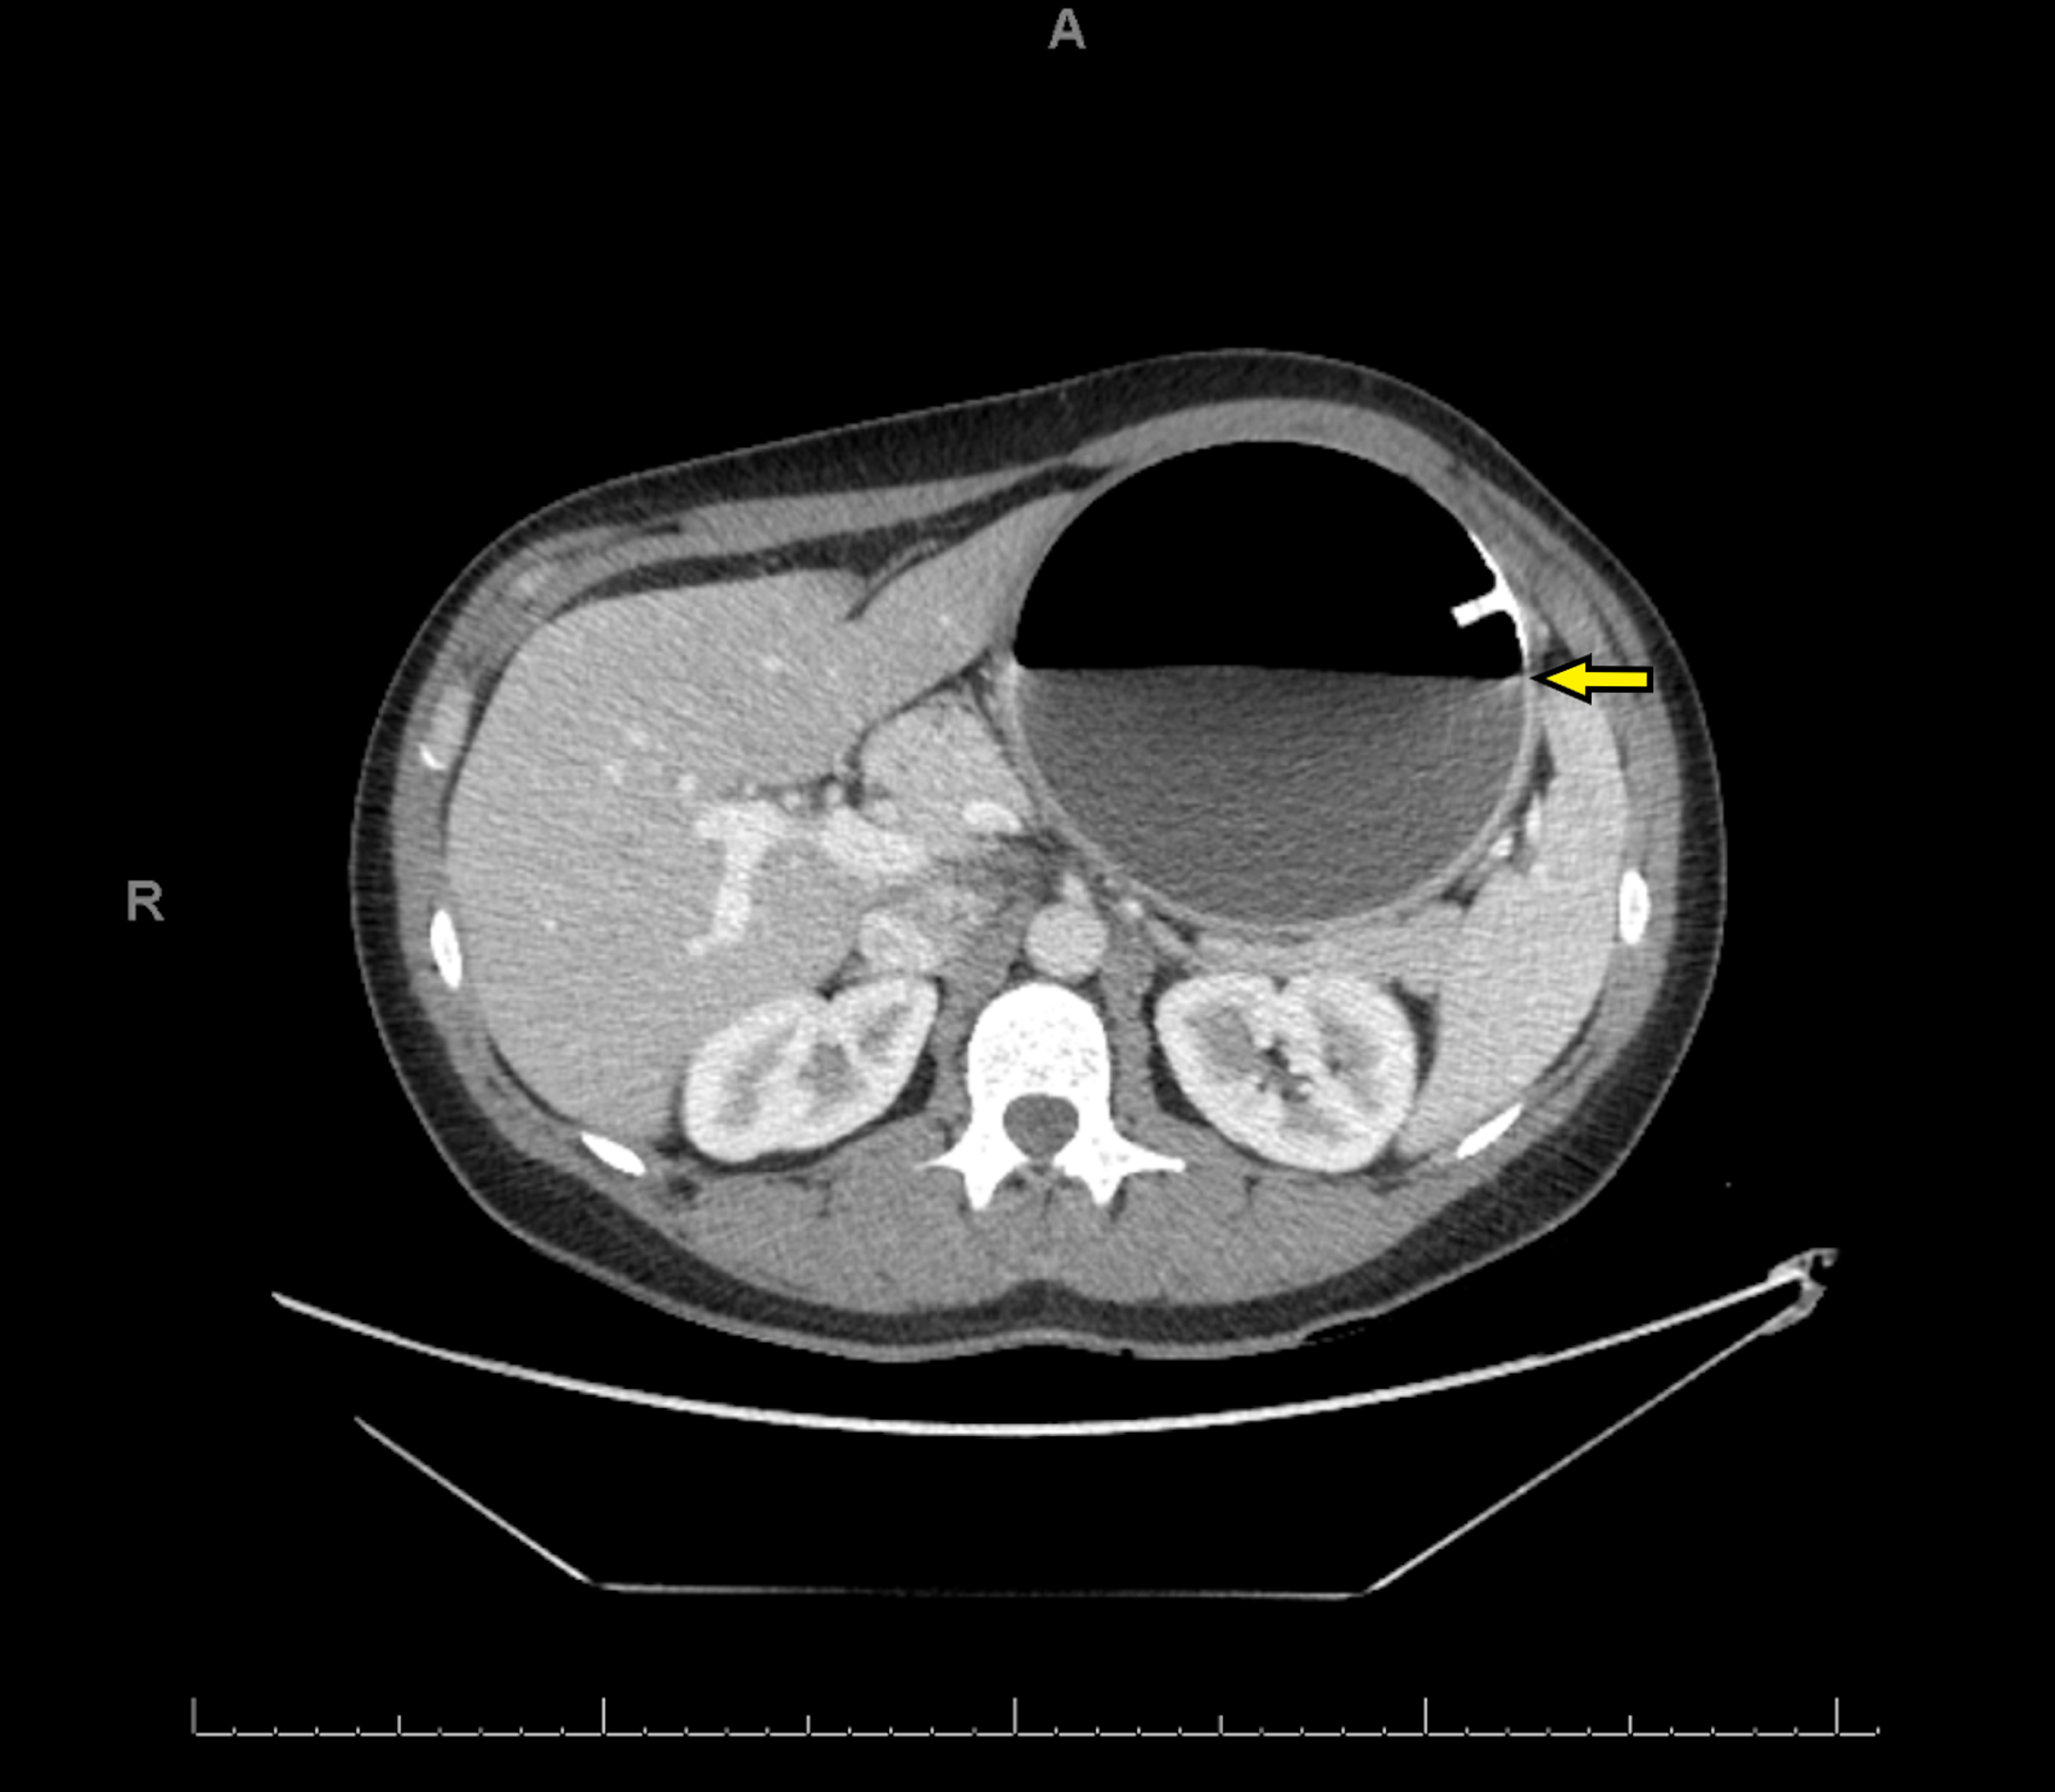

There is a gastric balloon in situ within the left upper abdomen, in the expected position of the stomach. Endoscopic bariatric techniques, such as the intragastric balloon (igb) have become an attractive alternative as a tool for weight loss,. Aside from weight progression under gastric balloon therapy and by using mri, our research paper describes the behavior of. Identify the major complications of these three forms of bariatric surgery and their relevant clinical features.

Gastric balloon, CT scan Stock Image C052/9874 Science Photo Library Gastric Balloon Radiology Identify the major complications of these three forms of bariatric surgery and their relevant clinical features. There is a gastric balloon in situ within the left upper abdomen, in the expected position of the stomach. Endoscopic bariatric techniques, such as the intragastric balloon (igb) have become an attractive alternative as a tool for weight loss,. Aside from weight progression under. Gastric Balloon Radiology.